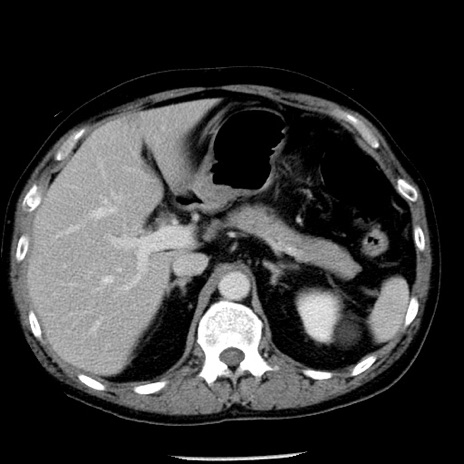

症例29(横断像)

【症例】40歳代男性

【現病歴】2日前から胃痛あり。徐々に周期的な激痛に変化した。本日になっても激痛があるため受診。

【身体所見】意識清明、BT 38-39℃台あり、腹部:膨満、やや硬、右下腹部に圧痛あり。

【データ】WBC 8500、CRP 23.26